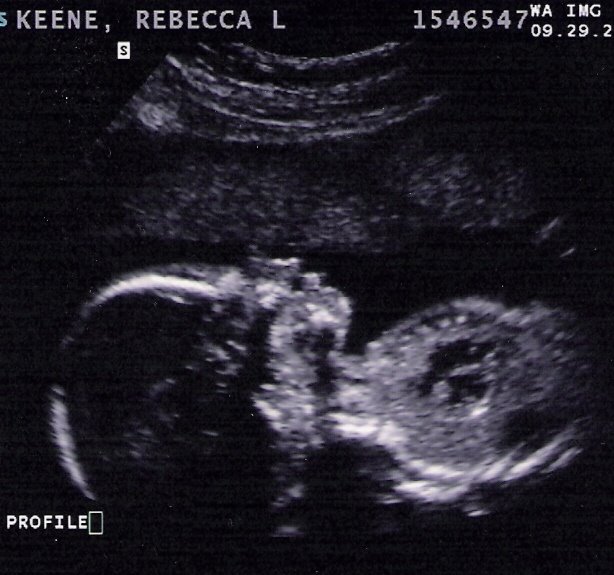

IT’S A BOY!

What a great day! We are so thankful to announce that our baby is a boy. While any healthy baby is a blessing, that is what we had hoped. Today we had an hour-long ultrasound. I had no idea the 20-week one was so intense. The technician measured bones, arteries, organs, and everything in between. Everything is functioning well and looks great. He measures a little ahead in size (6 days bigger than expected), but that doesn’t change my due date at all. His heart rate continues to sit around 150 bpm.

Are we sure it’s a boy, you ask? Yep! Since he likes to move around so much (both ultrasounds have confirmed what I have suspected for the last month, and both technicians have commented several times that we have a “very active baby”), it was hard to get a good shot of his boy anatomy at first. The technician pointed out some things and said she would proclaim with 80% accuracy that it was indeed a boy. A few minutes later, he turned, and she changed her odds to 90%. By the time he spread his legs and exposed himself all over the screen, we all laughed and the technician said “I’d say 95%… and that’s as high as I go!”